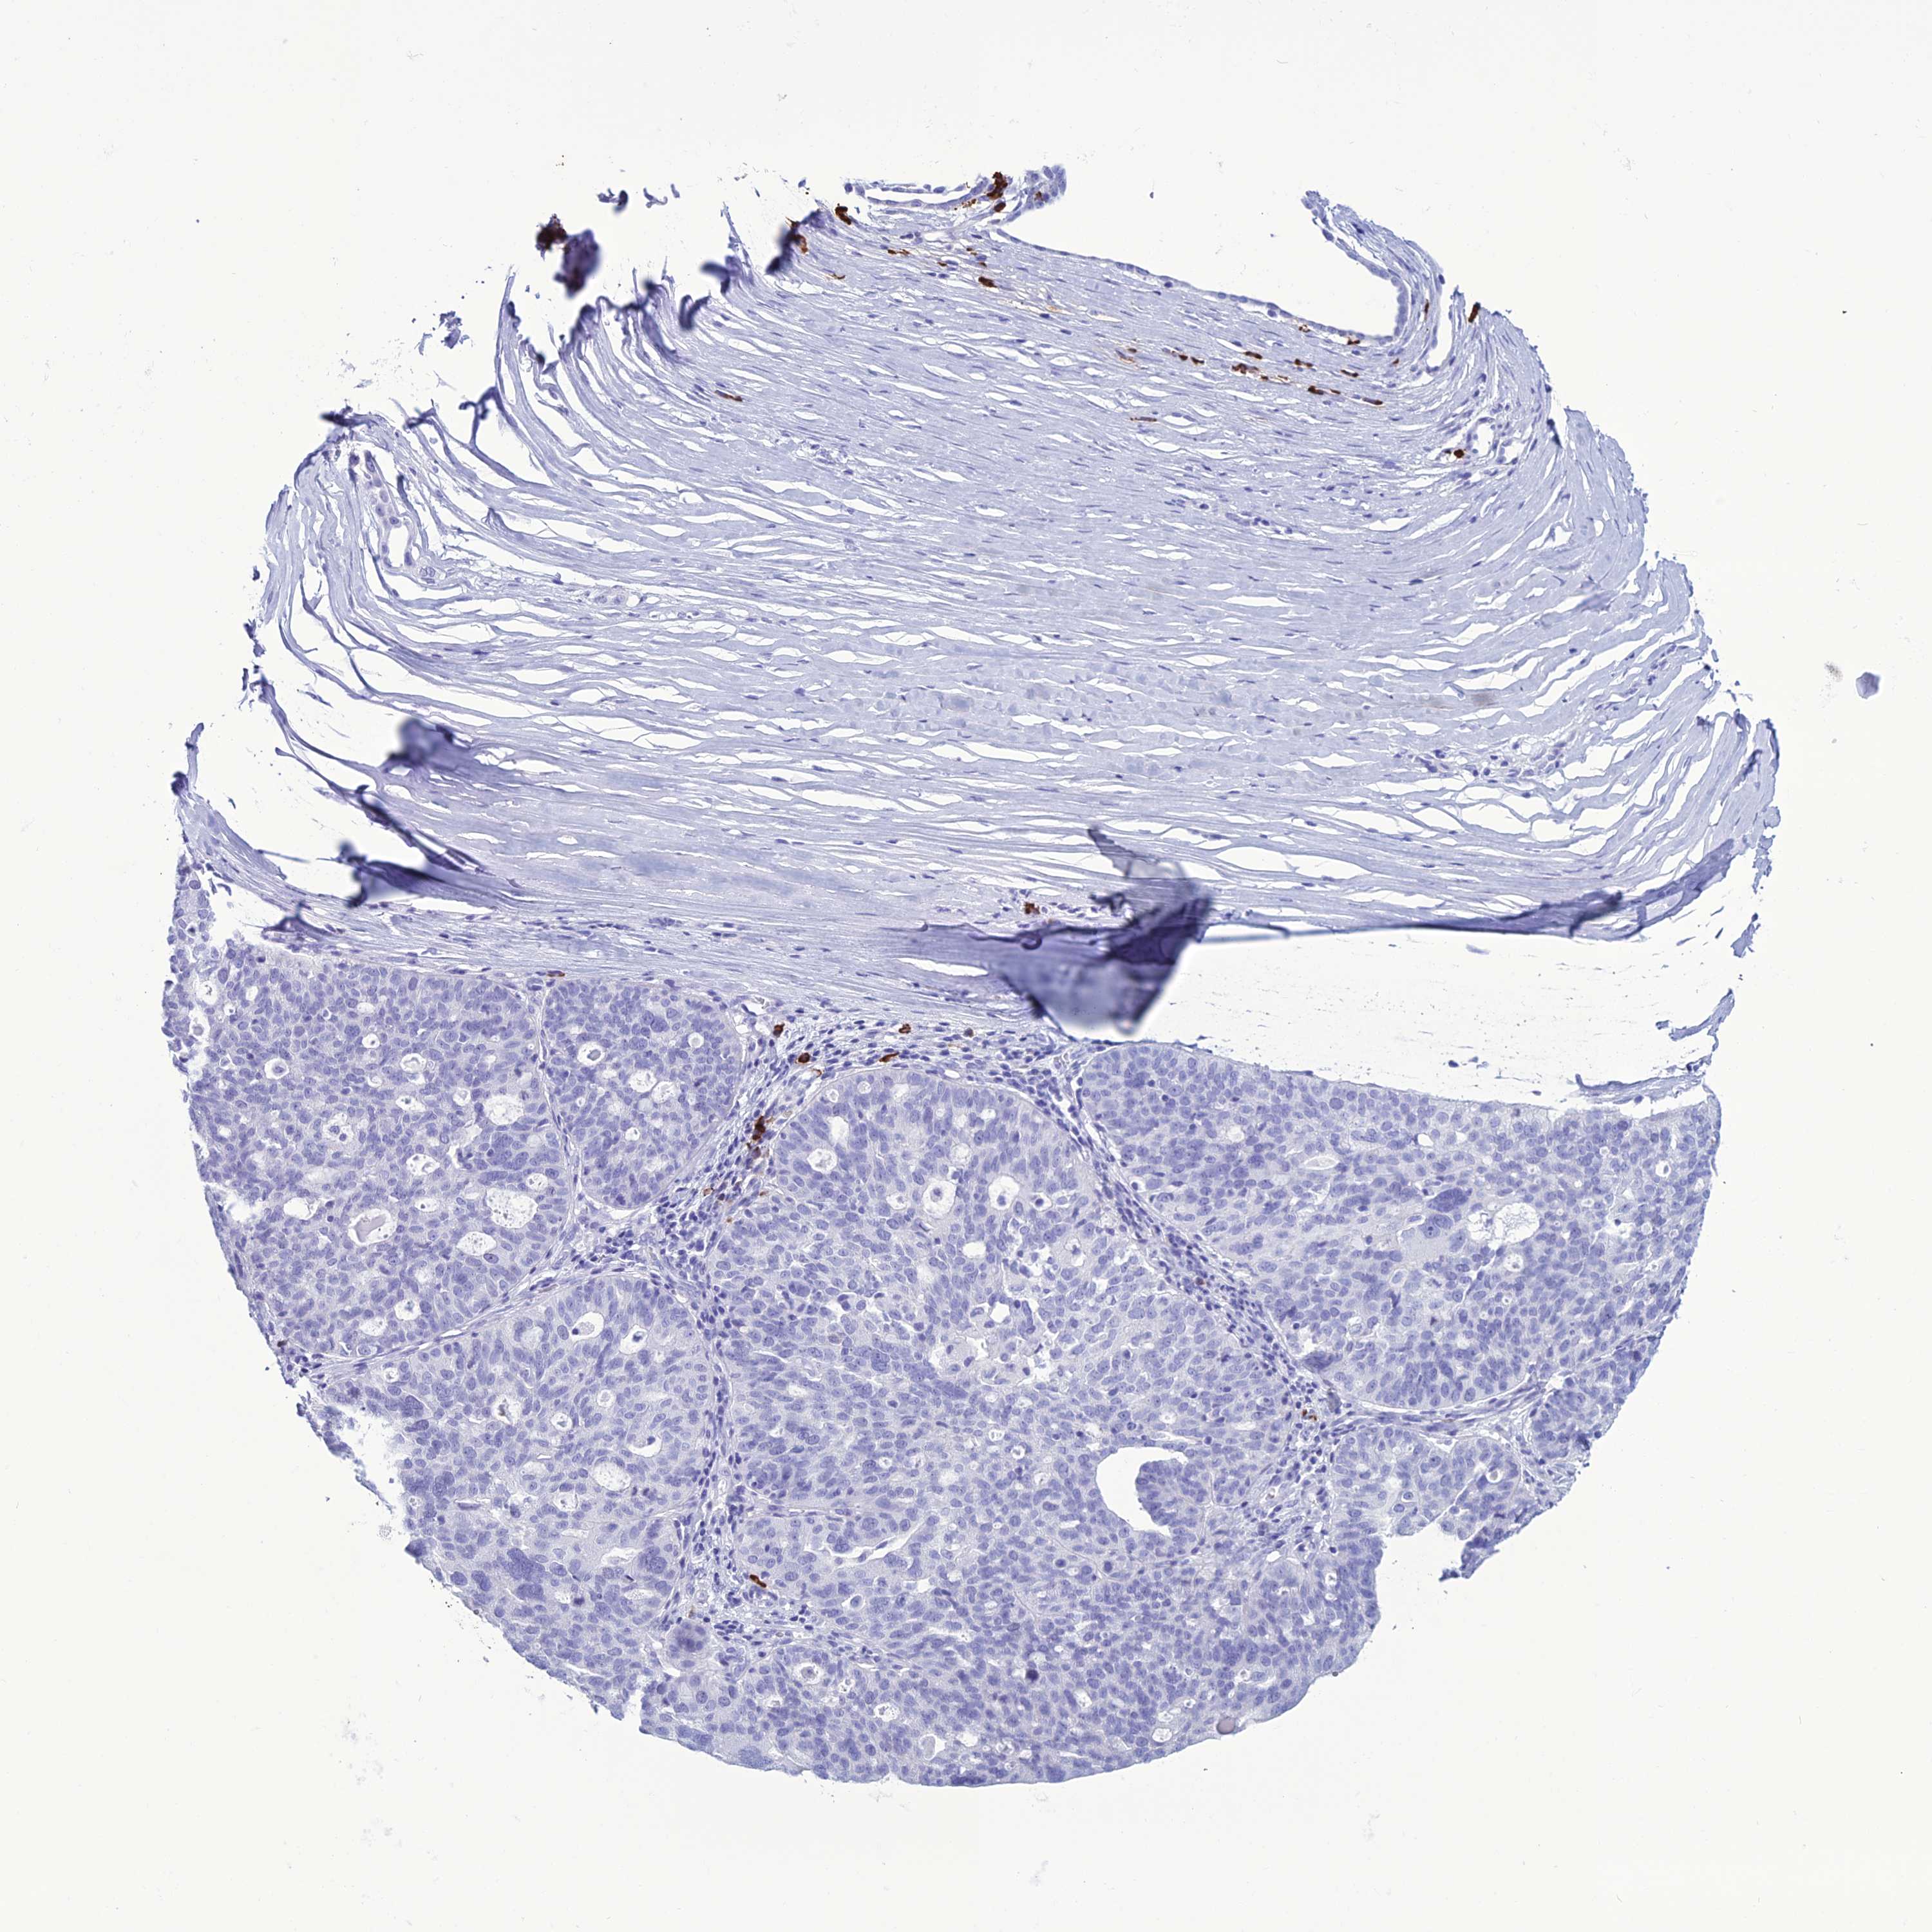

OVARIAN CANCER - Protein expressioni

A mouse-over function shows sample information and annotation data. Click on an image to view it in a full screen mode. Samples can be filtered based on level of antibody staining by selecting one or several of the following categories: high, medium, low and not detected. The assay and annotation is described here.

Note that samples used for immunohistochemistry by the Human Protein Atlas do not correspond to samples in the TCGA dataset.

Antibody stainingi

Antibody staining in the annotated cell types in the current human tissue is reported as not detected, low, medium, or high, based on conventional immunohistochemistry profiling in selected tissues. This score is based on the combination of the staining intensity and fraction of stained cells.

Each image is clickable and will lead to virtual microscopy that enables deeper exploration of all samples and also displays staining intensity scores, fraction scores and subcellular localization as well as patient and tissue information for each sample.

Antibody HPA043745

Antibody HPA052694

Cystadenocarcinoma, serous, NOS

Carcinoma, endometroid

Cystadenocarcinoma, mucinous, NOS

Carcinoma, NOS